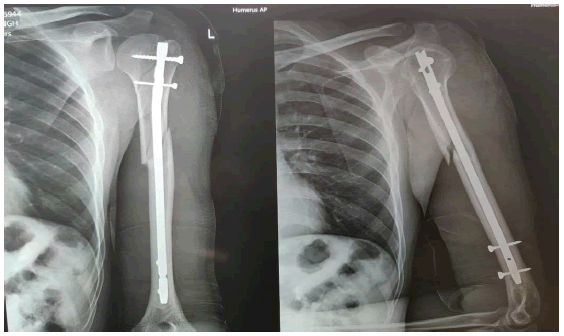

Humerus Nailing/Plating

Humerus nailing and plating are orthopedic surgical techniques used to treat fractures and other conditions affecting the humerus, which is the long bone in the upper arm.

• Humerus nailing is often done to stabilize fractures of the humerus. This can include fractures in the shaft (diaphysis) of the bone.

• Nailing is a minimally invasive technique that involves a smaller incision compared to traditional open surgery, leading to potentially faster recovery and reduced soft tissue damage.

• Intramedullary nailing facilitates rapid healing by stabilizing the fracture site and providing a supportive environment for bone union.